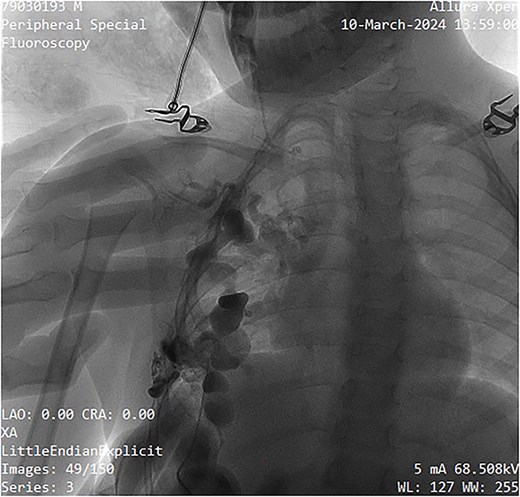

The sclerosing agent used was 3% polidocanol foam, prepared via Tessari’s technique. The foam formulation comprised 3 ml of polidocanol, 3 ml of normal saline, and 3 ml of air, totaling 9 ml. The non-radiopaque polidocanol was administered through the same needle. The contrast was subsequently ``washed out'' by the sclerosing agent, ensuring comprehensive treatment of all cystic spaces (Fig. 4). The procedure was done as a day case under local anesthesia with a support staff calming the patient. Pre- and post-procedure digital subtraction angiography images were obtained for mapping and completion. Post-instillation ultrasonography was performed to confirm adequate sclerotherapy distribution and to confirm extravasation did not occur. Compression taping was applied post-procedure, and the patient was discharged within a few hours on oral paracetamol as required.

Image showing sclerotherapy administration through the same needle used for contrast injection, effectively ``washing out'' the contrast while sclerosing the venous malformation.